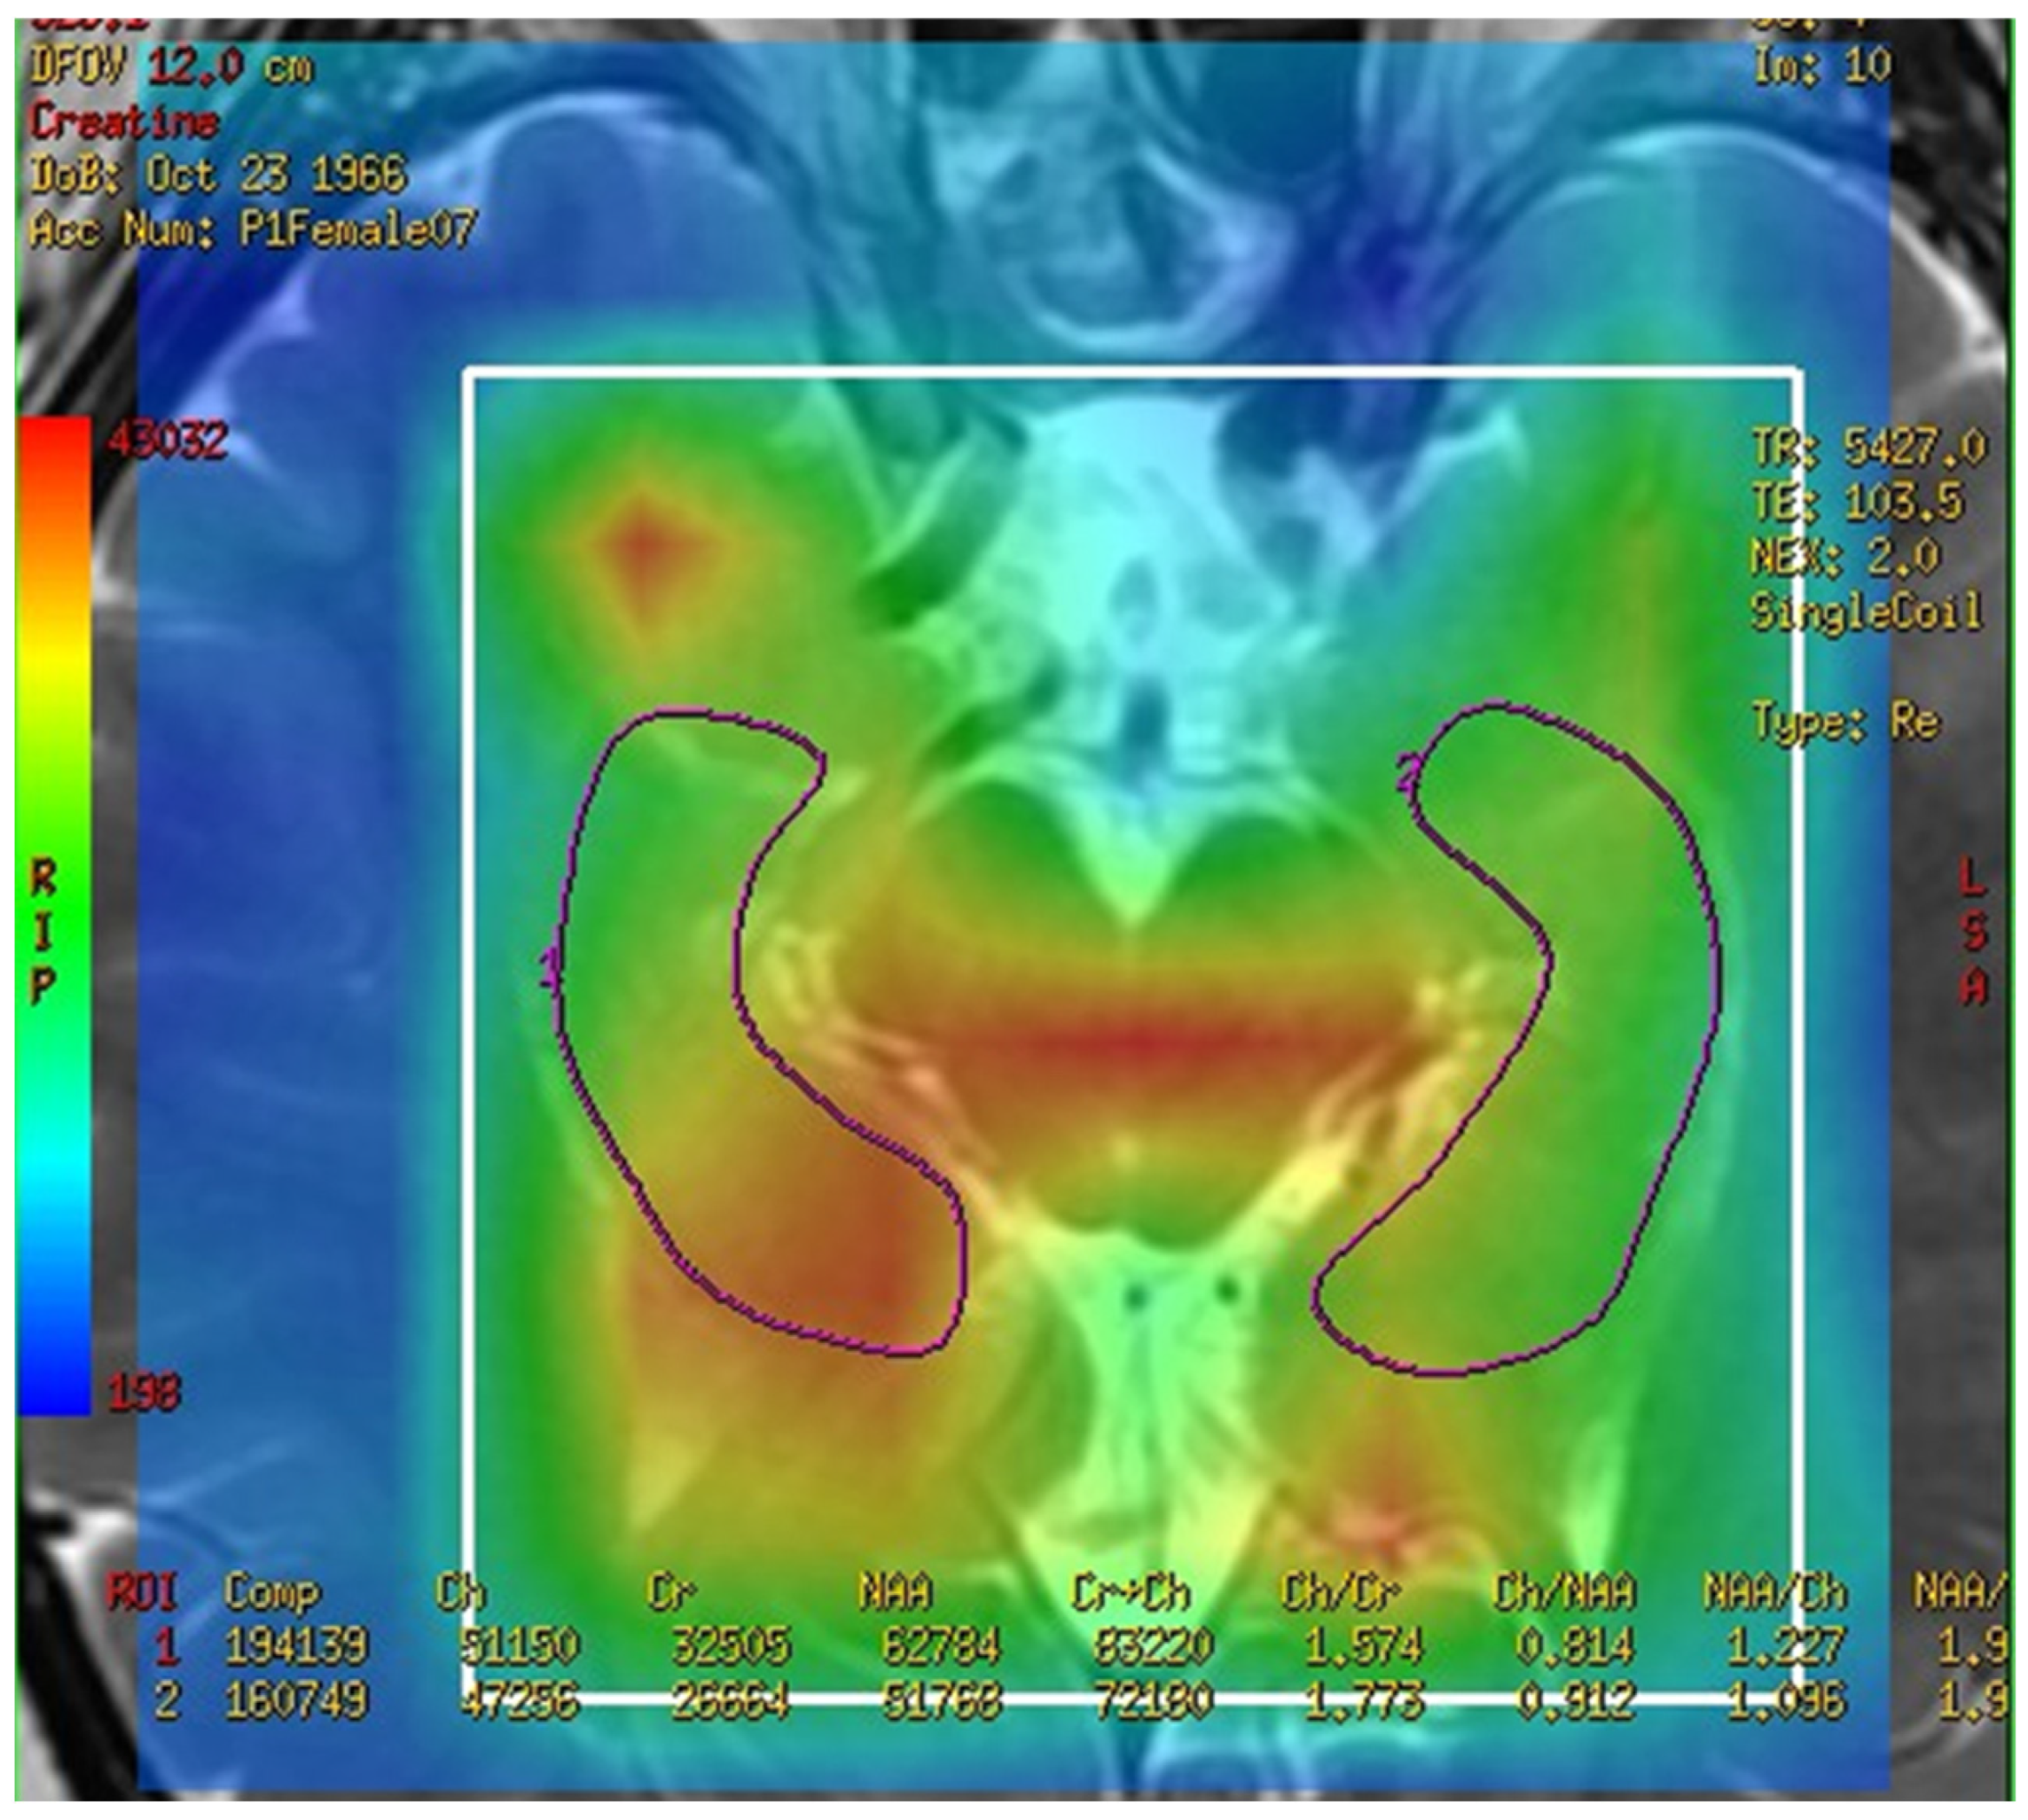

In this study, a medical 1.5 T MRI machine (GE Signa HDxt Medical Systems, Waukesha, WI, USA) and a standard head coil (Head Coil) in Camillians Saint Mary’s Hospital Luodong were used to receive signals from brain images of MRI T1 and T2 sequences, and 1H-MRS with 3D-CSI (echo time (TE) 144 ms, repetition time (TR) 1000 ms) for all participants. The range of chemical shift was set from 0 to 4 ppm, as this could include the signal of most metabolites in the brain, and the volume of each voxel was set at approximately 1–1.5 square centimeters. The measurements were performed as follows: First, brain images of T1 and T2 sequence with 3-Plane localization (sagittal, axial, and coronal planes) were obtained to locate the hippocampus and corpus callosum in the brain. Second, the three-dimensional space of the hippocampus and corpus callosum was manually marked and chosen on the image by a technician. Subsequently, the three-dimensional space of the hippocampus was divided into the total (bilateral), right, and left hippocampi. Third, the MRS with 3D-CSI was performed in the chosen location of the hippocampus (Figure 1) and corpus callosum (Figure 2). The signal intensities of choline (Cho), N-acetyl aspartate (NAA), creatine (Cr), and myo-inositol (MI) in the total (bilateral), right, and left hippocampi and the corpus callosum were measured and recorded in arbitrary units and used for statistical analysis.

Figure 1.

Magnetic resonance spectroscopy with three-dimensional chemical shift images in the chosen location of the left and right hippocampi (purple markup). The signal intensities of metabolites were measured and recorded.